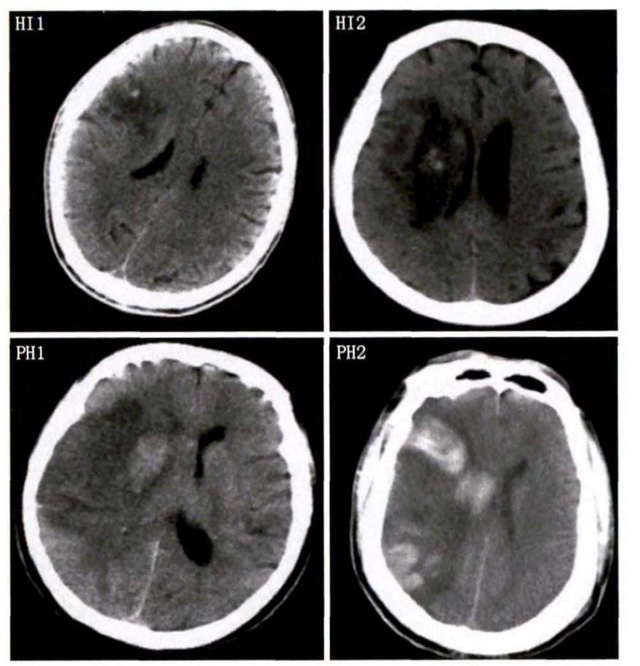

中、老年病患,有動脈粥樣硬化及高血壓病等腦卒中的危險因素,發(fā)病結(jié)合神經(jīng)系統(tǒng)癥狀和體征,應當考慮急性腦梗死的可能。再經(jīng)腦CT/MRI發(fā)現(xiàn)梗死灶,或排除腦出血、炎癥性疾病等,診斷即可確定。腦梗死有時頗似小量腦出血的臨床表現(xiàn)。腦栓塞在任何年齡都可以有發(fā)病的風險,可以在幾秒到幾分鐘達到頂峰。會有偏癱不能說話等局部神經(jīng)功能損壞。栓子來源很種,可能是冠心病、心肌梗塞、心內(nèi)膜炎等。合并心房纖顫,結(jié)合其他臟器官的支持診斷,CT跟磁共振都可以檢查確定栓塞位置數(shù)量還有是不是有伴發(fā)出血等問題。可以幫助診斷。

中老年患者,多有高血壓病史,情緒激動發(fā)病,神經(jīng)功能缺損癥狀、頭痛、嘔吐、顱高壓癥狀,腦出血的可能,CT或者磁共振的檢查,可以迅速明確診斷。蛛網(wǎng)膜下腔出血的診斷依據(jù)有哪些?突然的頭疼劇烈,有惡性嘔吐現(xiàn)象,腦膜刺激征陽性,有意識障礙。無局灶性神經(jīng)系統(tǒng)體征,那么有可能是蛛網(wǎng)膜下腔出血。CT或者磁共振證實蛛網(wǎng)膜下隙高密度征象或血性腦脊液等可臨床確診。